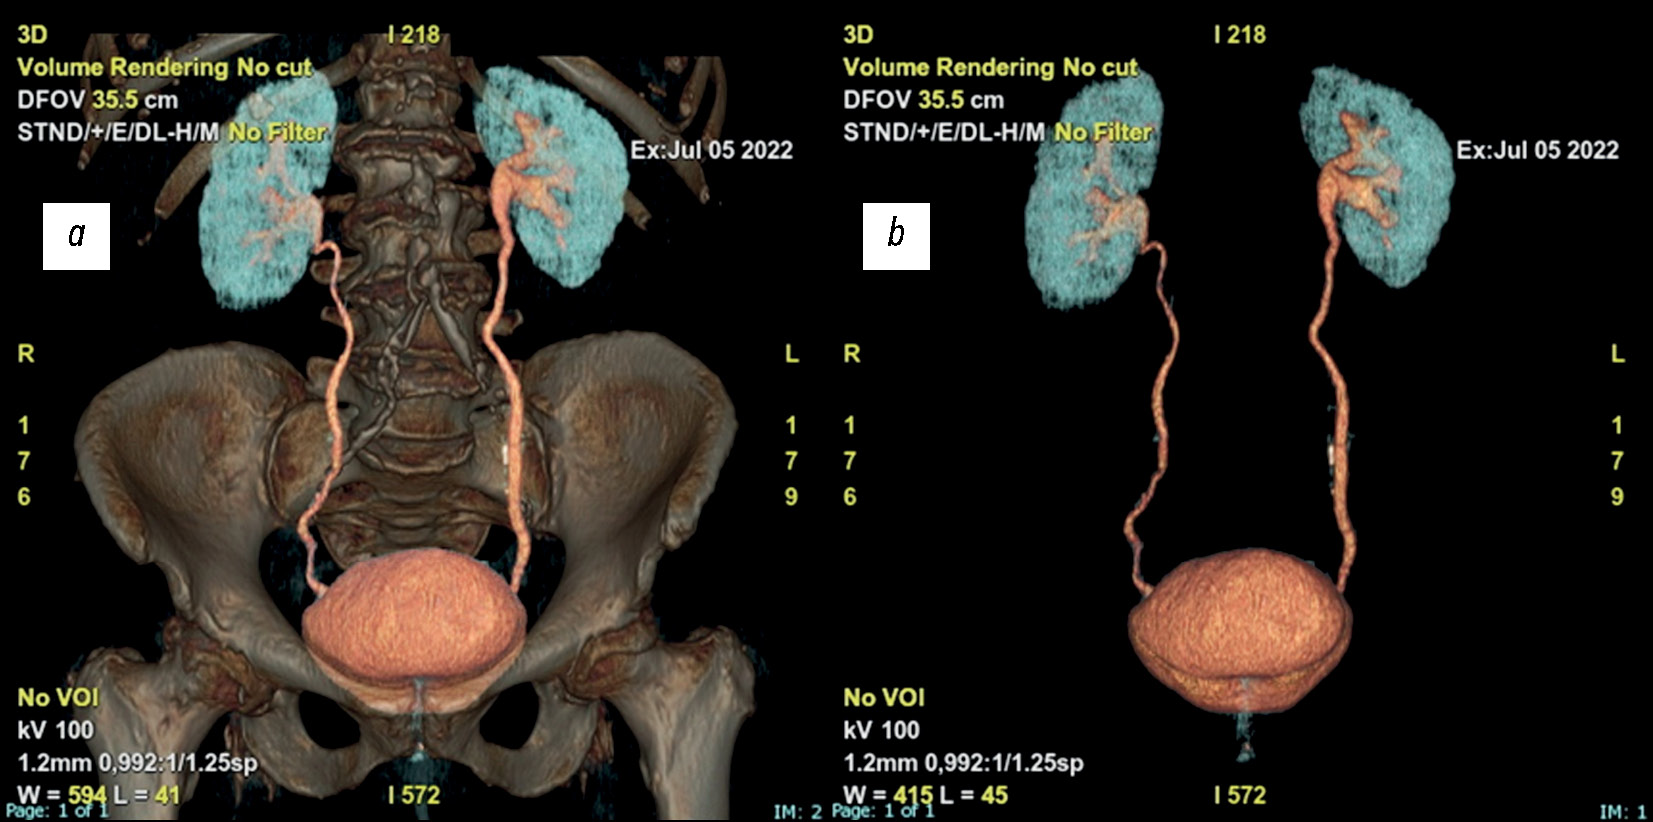

На основании результатов КТ можно выполнить трёхмерную реконструкцию мочевыводящих путей. Такой подход, сформировавшийся в результате эволюции классической урографии, позволяет выполнить полную визуализацию мочевыделительной системы, получить информацию о морфологических характеристиках и функциональности почек и мочевыводящих путей, выявить пороки развития, конкременты или солидные новообразования. Трёхмерная реконструкция показана для установления причины гематурии, выявления опухоли почки, мочеточника или мочевого пузыря, или для выявления и локализации камня при наличии соответствующего болевого синдрома (рис. 2).

Рис. 2. Трёхмерная реконструкция по данным компьютерной томографической урографии с контрастированием: a — с визуализацией; b — без визуализации костей на фоне в коронарной плоскости.